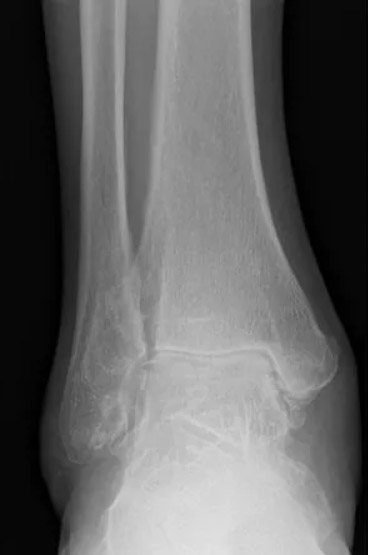

Example of x-rays showing advanced (end-stage) arthritis. Compared to the photo below (of a healthy ankle), the joint space is significantly narrowed or absent and there are many bone spurs throughout.

Example of a normal, healthy ankle joint with preserved joint space with no arthritis (the dark space between the red arrows)